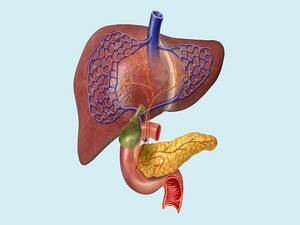

His special interests are in the field of Laparoscopic Hernia Surgery, Laparoscopic Upper G.I Surgery, Laparoscopy in Gastrointestinal Cancers and Bariatric Surgery. He is also actively involved in publications in peer – reviewed journals.